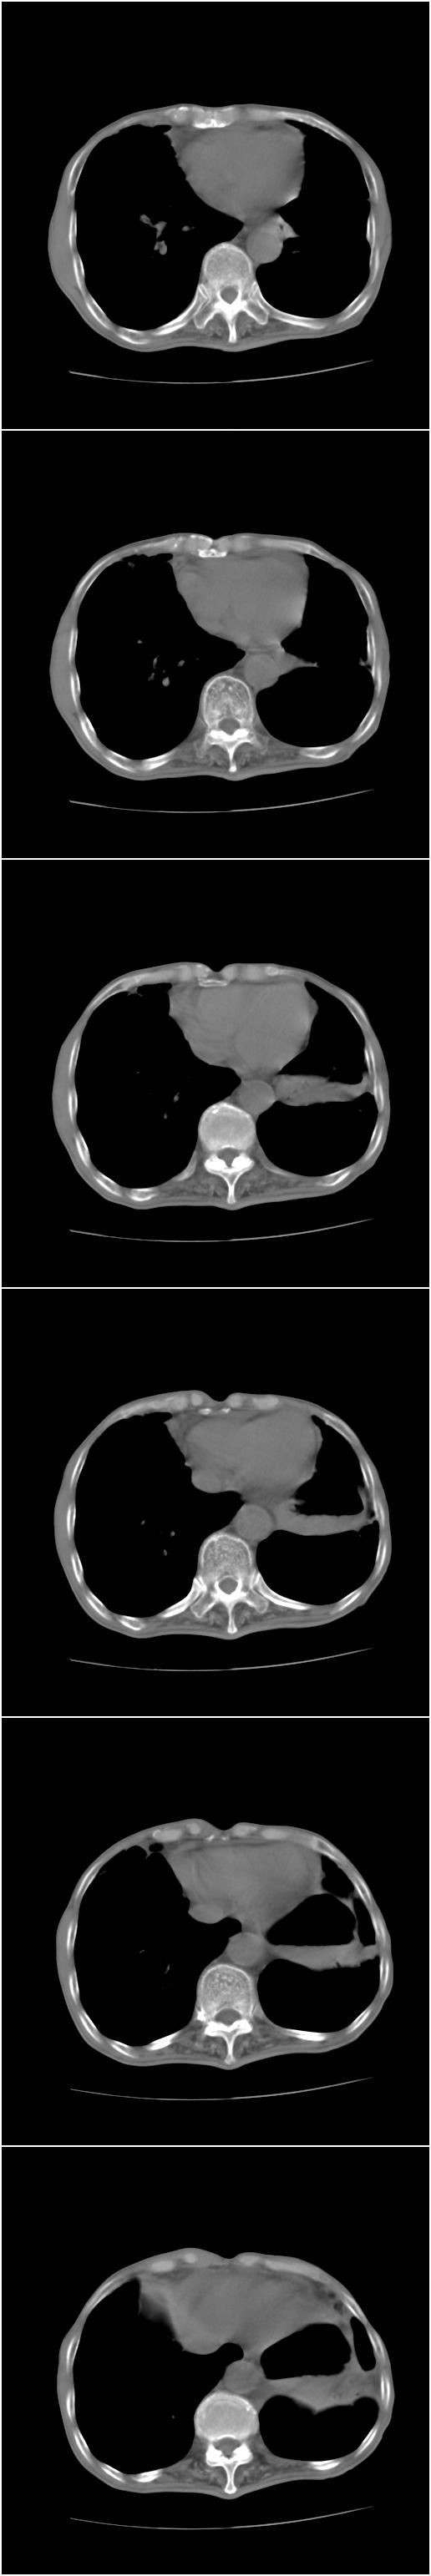

标题: CT12024:男,77岁。咳嗽两月余,气喘一月,13年前岑作贲门 [打印本页]

标题: CT12024:男,77岁。咳嗽两月余,气喘一月,13年前岑作贲门

1、右侧中心型肺癌,右肺门,纵隔淋巴结转移可能性大。

2、贲门癌术后所见。

右侧中心型肺癌,右肺门,纵隔淋巴结转移。

右中心型肺癌 纵隔淋巴结转移

右侧中央型肺癌伴右肺门及纵隔淋巴结转移.

1 右肺中心型肺癌伴右肺门及纵隔淋巴结转移.

2  左肺贲门癌术后改变.

1)考虑为:右侧中心型肺癌并右肺门及纵隔淋巴结转移。2)贲门癌术后改变。